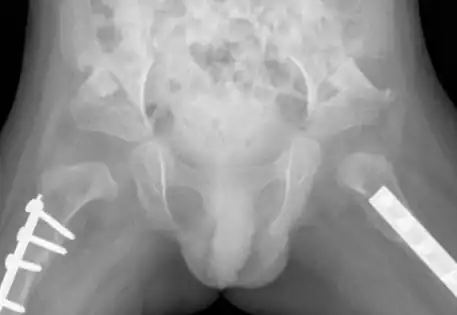

Clinical Case A : 2 year old girl presenting with left dislocated hip

What is the outcome following single-stage hip reconstruction?

Surgical outcomes for late-presenting hip dislocations are typically associated with the age of diagnosis, with less favorable results reported for older children in the literature. Dr. Qureshi employs a single-stage hip reconstruction technique, addressing all deformity elements comprehensively rather than solely focusing on hip relocation. Dr. Qureshi is pleased to showcase successful cases treated with this advanced approach.